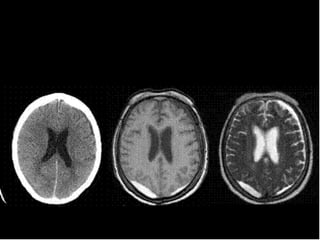

Hematoma Subdural

 Sangre entre la dura y la aracnoides

 No hay relacion con fracturas

 Forma semilunar

 Cruza las suturas, pero no las inserciones

durales

 T.A.C. fase aguda = coleccion hiperdensa

 I.R.M.detecta hematomas muy pequenos

Hematoma Epidural

   T.A.C. hiperdenso, heterogeneo precoz, se vuelve

homogeneo en pocas horas

   85% al 95% se asocia a fractura craneal

Hematoma Subdural  Sangreentre la dura y la aracnoides  No hay relacion con fracturas  Forma semilunar  Cruza las suturas, pero no las inserciones durales  T.A.C. fase aguda = coleccion hiperdensa  I.R.M.detecta hematomas muy pequenos

Hueso dura aracnoides pia Cerebro Hematoma subdural concavo en su margen interno

Hematoma Epidural  Mayorincidencia en ninos que en adultos, de origen venoso  Forma biconvexa, lenticular  No cruza suturas, si inserciones durales  T.A.C. hiperdenso, heterogeneo precoz, se vuelve homogeneo en pocas horas  85% al 95% se asocia a fractura craneal  Frecuentemente provoca herniaciones